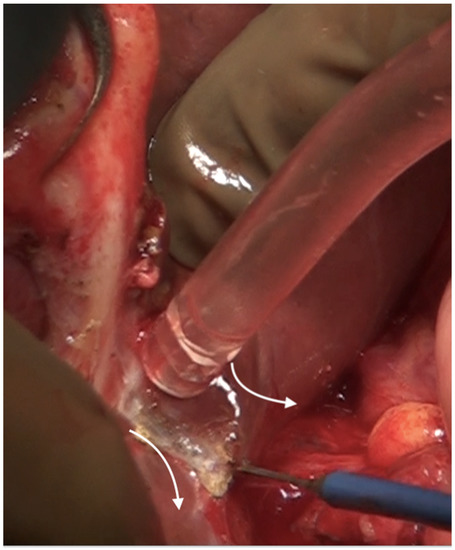

6.3. Glissonectomy

6.4. Left Subphrenic Peritonectomy and Central Diaphragmatic Peritonectomy